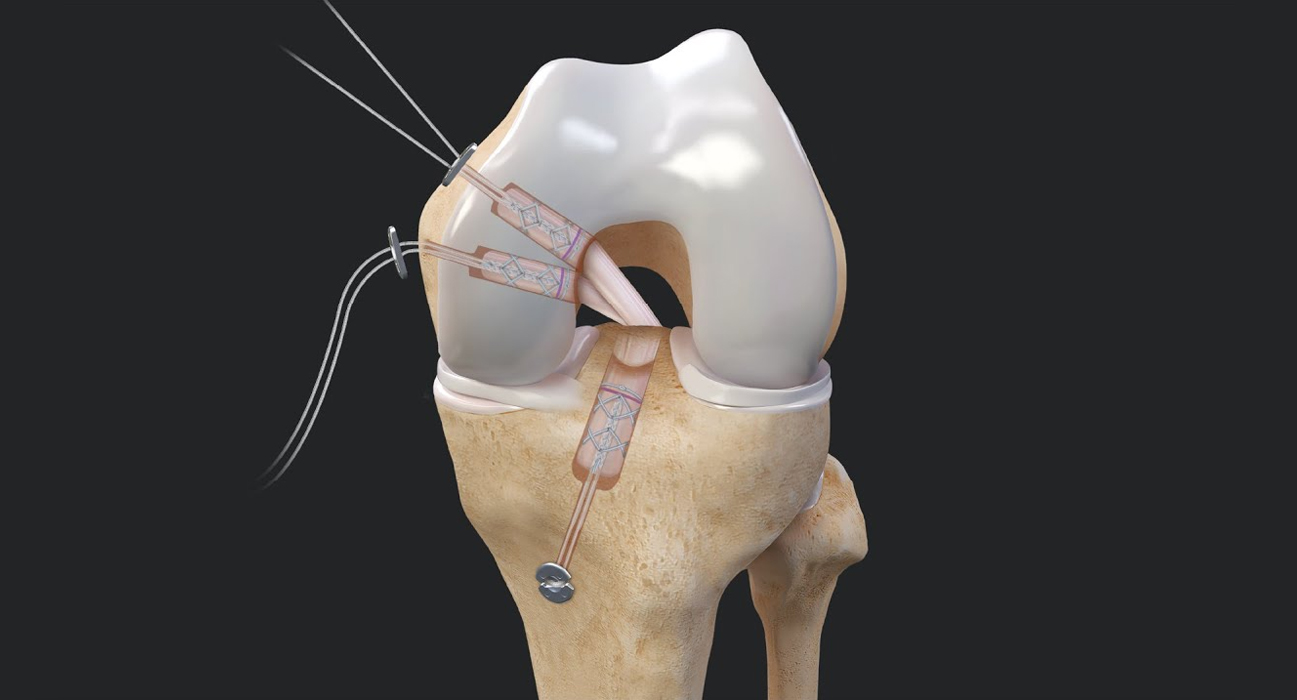

Arthroscopy is a surgical procedure orthopaedic surgeons use to visualize, diagnose, and treat problems...

Arthroscopic shoulder surgery is a procedure done by orthopedic surgeon to visualise, diagnose and repair problems in the shoulder joints. This surgery is performed using a small camera called an arthroscope. The Arthroscope contains a light source and magnifying lenses to capture the images of the joints. The camera is inserted through small incisions of the skin.

ACL tears affect millions of people each year worldwide, making them one of the most common knee injuries. Athletes and active individuals ....